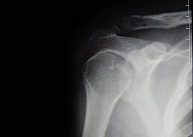

Las fracturas de clavícula representan del 10 al 16% de todas las fracturas de nuestro esqueleto y son las fracturas más frecuentes de la infancia. Afectan fundamentalmente a su tercio medio (75%) y no suelen producirse por impacto directo sobre ella, sino, por una caída sobre el hombro, el cual transmitela fuerza deformante hacia la clavícula produciendo su fractura.Este tipo de lesión es característico, pues, de aquellos deportes que pueden provocar impactos violentos sobre el hombro como caídas desde bicicleta, motocicleta, patín, skate o deportes de contacto como rugby, hockey hielo, futbol americano, etc.

Con la finalidad de una rápida incorporación a la actividad deportiva proponemos siempre que sea posible una intervención mínimamente invasiva con una estabilización rápida a través de una pequeñísima incisión que garantiza una menor probabilidad de complicaciones.